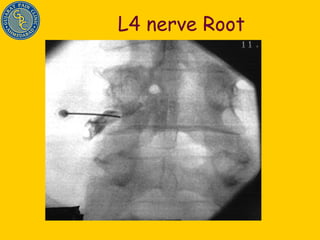

L4 nerve Root